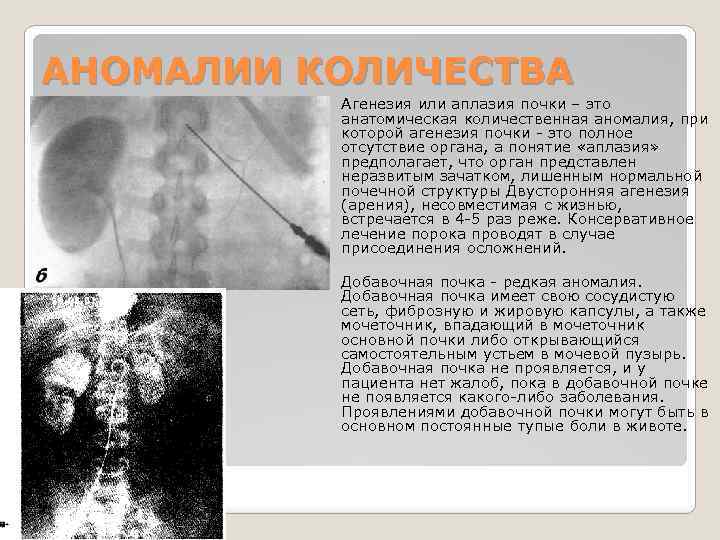

АНОМАЛИИ КОЛИЧЕСТВА Агенезия или аплазия почки – это анатомическая количественная аномалия, при которой агенезия почки - это полное отсутствие органа, а понятие «аплазия» предполагает, что орган представлен неразвитым зачатком, лишенным нормальной почечной структуры Двусторонняя агенезия (арения), несовместимая с жизнью, встречается в 4 -5 раз реже. Консервативное лечение порока проводят в случае присоединения осложнений. Добавочная почка - редкая аномалия. Добавочная почка имеет свою сосудистую сеть, фиброзную и жировую капсулы, а также мочеточник, впадающий в мочеточник основной почки либо открывающийся самостоятельным устьем в мочевой пузырь. Добавочная почка не проявляется, и у пациента нет жалоб, пока в добавочной почке не появляется какого-либо заболевания. Проявлениями добавочной почки могут быть в основном постоянные тупые боли в животе.

АНОМАЛИИ КОЛИЧЕСТВА Агенезия или аплазия почки – это анатомическая количественная аномалия, при которой агенезия почки - это полное отсутствие органа, а понятие «аплазия» предполагает, что орган представлен неразвитым зачатком, лишенным нормальной почечной структуры Двусторонняя агенезия (арения), несовместимая с жизнью, встречается в 4 -5 раз реже. Консервативное лечение порока проводят в случае присоединения осложнений. Добавочная почка - редкая аномалия. Добавочная почка имеет свою сосудистую сеть, фиброзную и жировую капсулы, а также мочеточник, впадающий в мочеточник основной почки либо открывающийся самостоятельным устьем в мочевой пузырь. Добавочная почка не проявляется, и у пациента нет жалоб, пока в добавочной почке не появляется какого-либо заболевания. Проявлениями добавочной почки могут быть в основном постоянные тупые боли в животе.